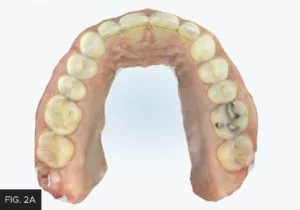

Once the orthodontic goal of the treatment plan was achieved, the restorative phase entailed the closure of the midline diastema and lengthening and recontouring of teeth #8 and 9. Itero (Align technology) scans of the maxillary and mandibular arches (FIG. 2A, 2B) were obtained from which diagnostic models were fabricated.

Scans of the mandibular and maxillary arches were obtained. Models were made from these and mounted. Wax-ups of the ideal restorative result were then fabricated on these mounted models.